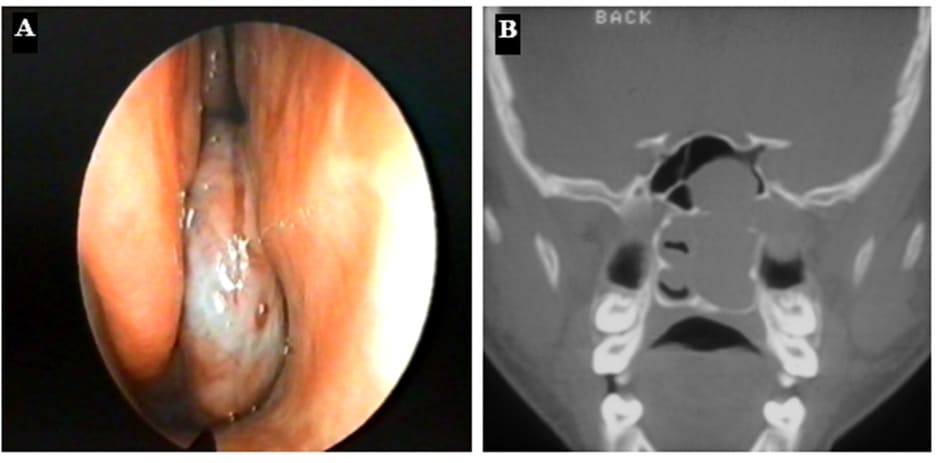

Figure 13: (A) Endoscopic view of a JNA in the posterior part of the right nasal cavity. (B) Coronal CT-scan of a patient with a JNA on the left side: complete nasal obstruction, bulging in the sphenoid sinus and widening of the pterygopalatine fossa.